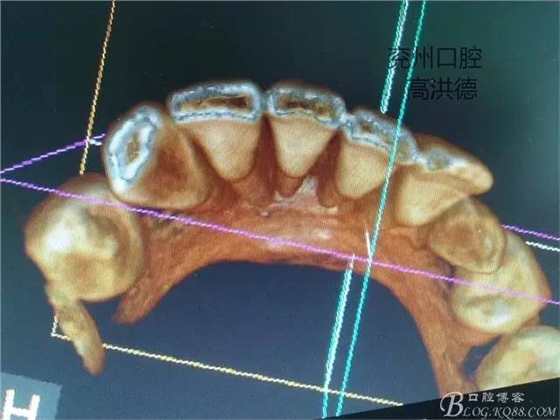

三維成像

冠狀位,舌側(cè)觀